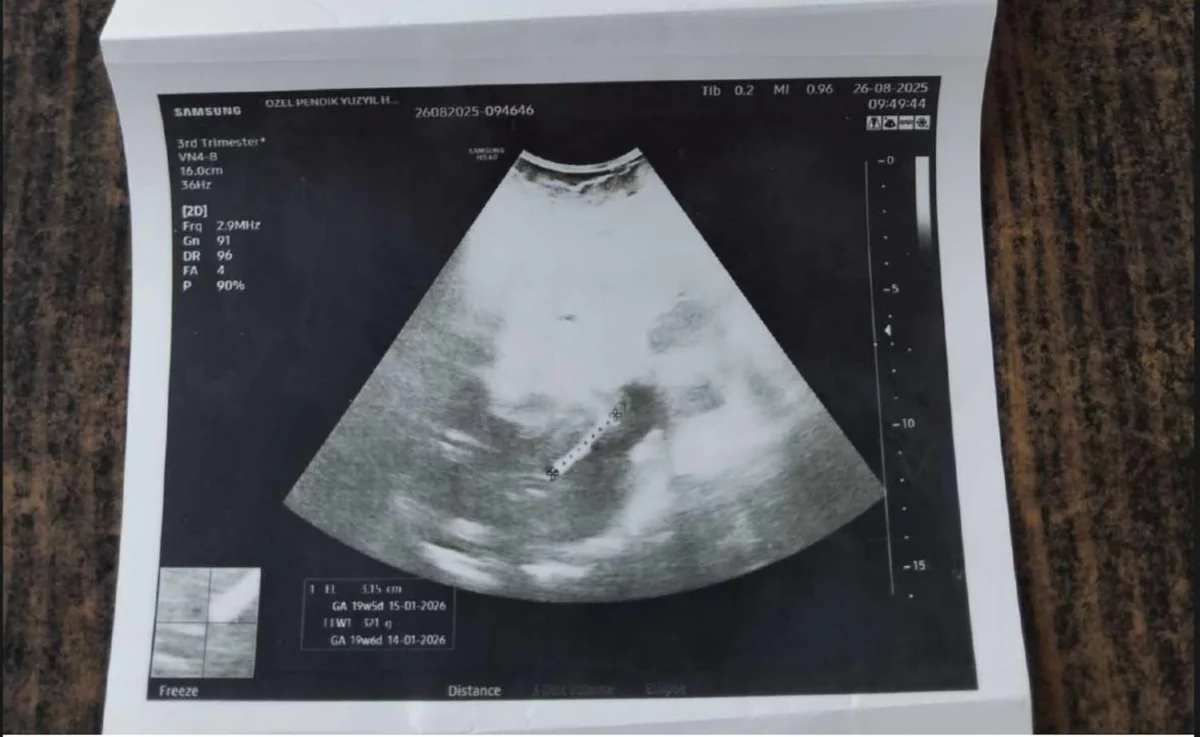

Hamilelik ve sağlık riski

Omarova’nın sağlık problemlerine zorunlu olarak değinmek gerekiyor. Bu problemler arasında şunlar bulunuyor: Umbilikal herni (göbek fıtığı) hastalığı var, bağırsaklarının bir bölümü dışarıya sarkmış durumda. Çeşitli vitamin eksikleri mevcut. D vitamini, magnezyum, demir eksikliği ile ilgili tedavi görüyor.